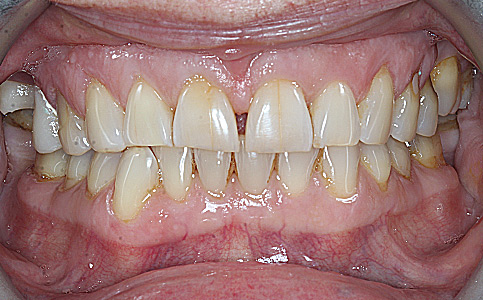

Pacjent zgłosił się do naszej kliniki ponieważ marzył o pięknym uśmiechu. Jego metamorfoza była wielospecjalistyczna. Pierwszym etapem było leczenie biologiczne, następnie uzupełnienie braków zębowych implantami oraz wykonanie koron pełnoceramicznych na zęby górne. Dzięki temu Pacjent odzyskał pewność siebie i zdrowy uśmiech.